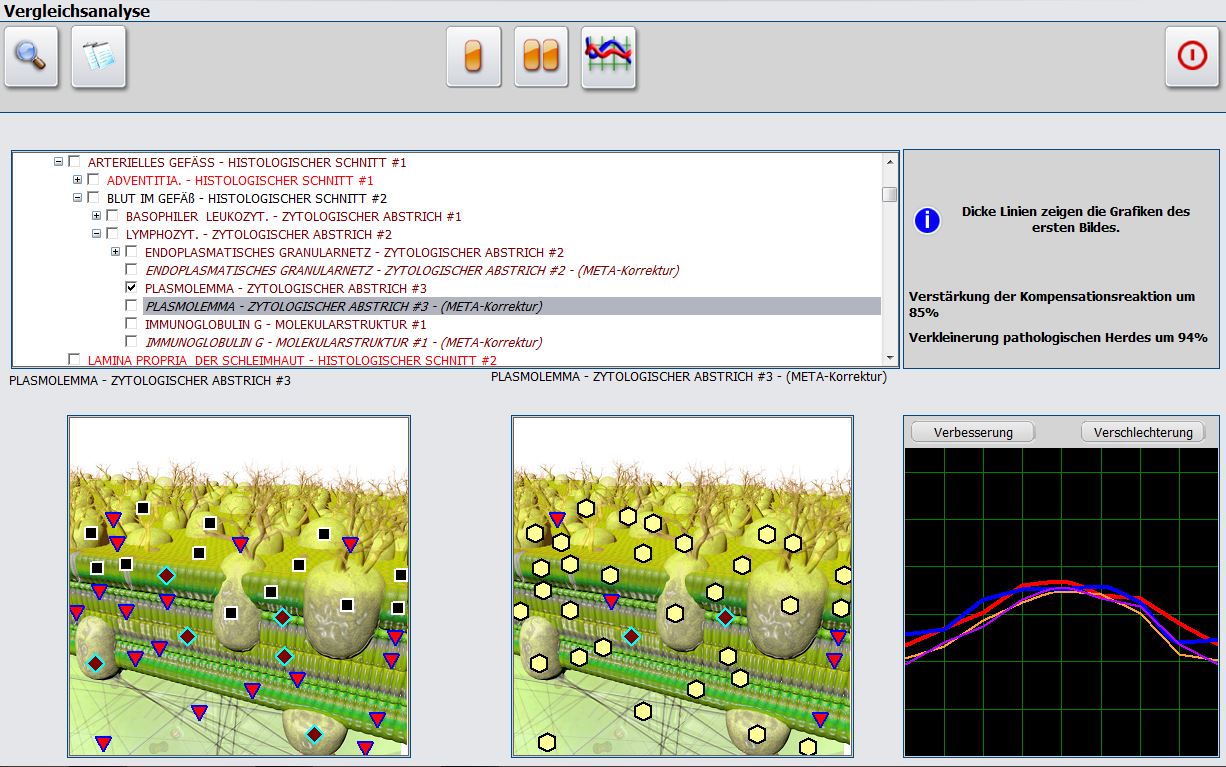

Präparateherstellung in der nichtlinearen Systemdiagnostik und -therapie

Analyse eines Therapievergleichs in der nichtlinearen Systemdiagnostik und -therapie

Einsatz verschiedener NLS-Systeme zur Fehlerminimierung und Vergleich mit herkömmlichen diagnostischen Verfahren wie der Magnetresonanz-tomografie (MRT) und Röntgen